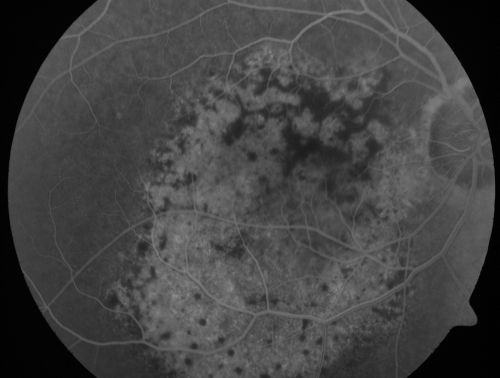

Pigmented Choroidal Mass Right Eye - Melanoma vs. Nevus vs. Unilateral Melanocytic Proliferation - 4 Month Follow-Up Images

71-year-old man his vision 4 month follow-up.  Vision is 20/60 and patient sees flashing lights.  Lesion has grown slightly in the superior half of the macula.